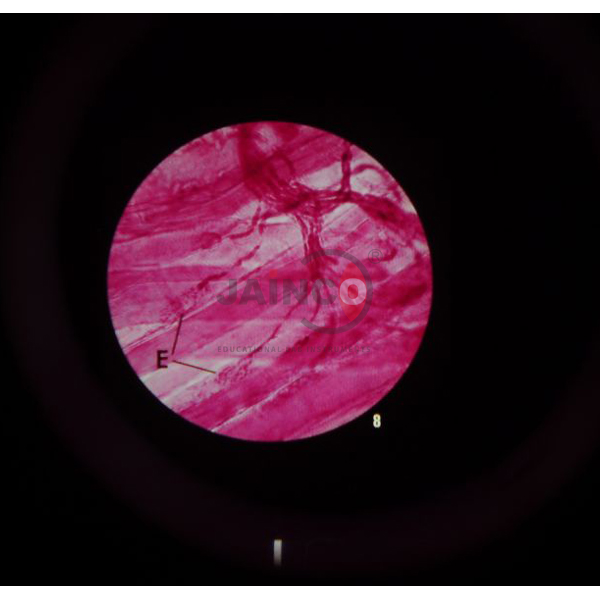

Microslides are sets of 8 related 35mm images as photographed through a microscope to be viewed through a Microslide Viewer Jainco.

Arrows and callouts help the students locate important features being studied.

Pacinian corpuscle (360x), Spinal ganglion & nerve, Pacinian corpuscle (80x), Spinal cord & nerve, Motor neuron, Spinal cord, Grey matter, Motor end plates.